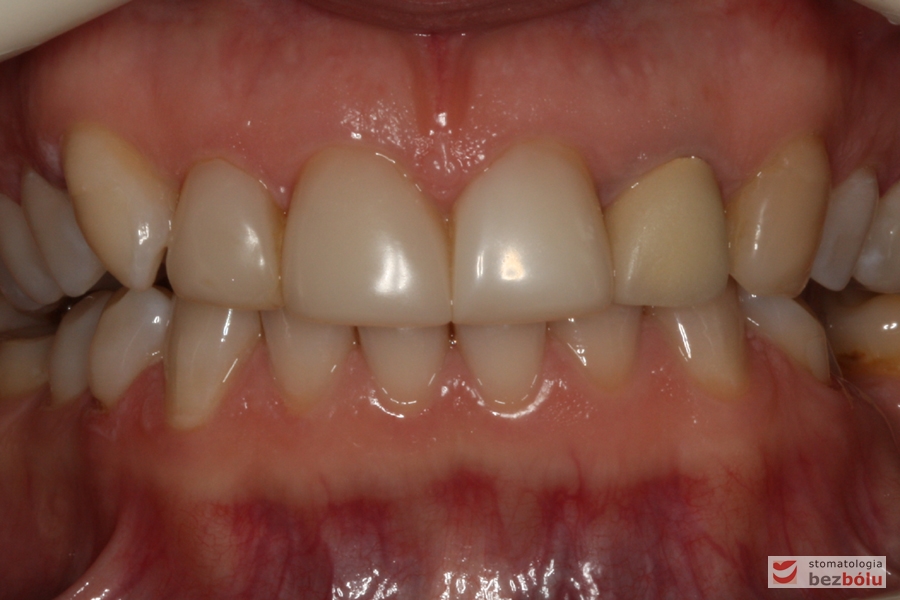

Zęby w zwarciu - widok frontalny, kieł prawy nie osiąga płaszczyzny okluzyjnej, nieregularna linia dziąsłowa

Zęby w zwarciu – widok frontalny, kieł prawy nie osiąga płaszczyzny okluzyjnej, nieregularna linia dziąsłowa